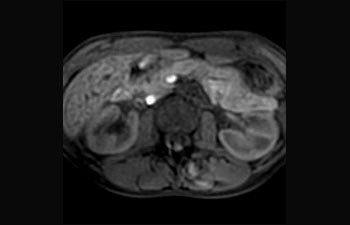

Find the right clinical applications for your needs